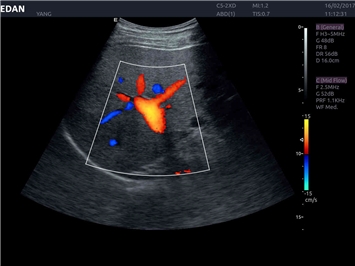

Трехмерная реконструкция ЦДК:

Да

Энергетический допплер:

Цветовой допплер:

Импульсно-волновой допплер: